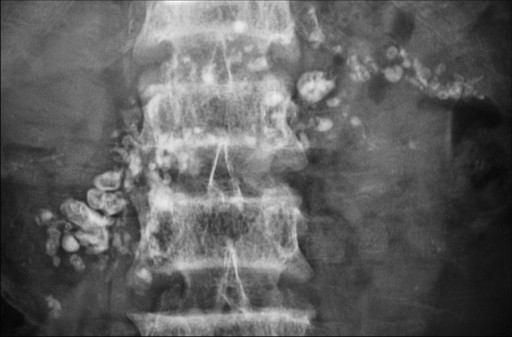

Tropical calcific pancreatitis was diagnosed when there were unique clinical, biochemical and radiological features. These included: i) recurrent abdominal pain; ii) diabetes mellitus; iii) large ductal calculi seen on plain film and other imaging tools (Figure 4) and iv) no history of alcohol or other metabolic or structural causes of chronic pancreatitis. The control group included patients in whom ERCPs had been performed but were found to have diseases unrelated to the biliary tract or pancreas. Alcohol-induced chronic pancreatitis included patients in whom ERCPs showed features of chronic pancreatitis and were etiologically related to alcohol as per the above-mentioned criteria [24, 25].

Figure 4. Tropical calcific pancreatitis. Plain film of the abdomen showing extensive large radio-opaque shadows (calculi) in the entire pancreatic region. |